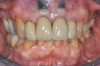

Fig 9. Completed crowns at 5 years, front view. Implant No. 9 was screw-retained (periodontist: Robert A. Levine, DDS; restorative dentist: Zola Makrauer, DMD).

Figure 9

Fig 10. Completed crowns at 5 years, angled view. Note the convex contours facial to implant No. 9 attributed to the connective tissue grafting.

Figure 10

Figure 8 shows the provisionalization of No. 8 at 6 weeks postoperatively and a screw-retained provisional restoration on No. 9 to develop the subgingival transitional zone (key Nos. 8 through 10). The transitional zone will be duplicated using the custom impression coping technique. Figure 9 and Figure 10 depict the completed crowns at 5 years; implant No. 9 was screw-retained (key No. 10). In Figure 10 note the convex contours facial to implant No. 9 that are attributed to the connective tissue grafting as part of the surgical protocol creating biotype conversion from a thick to a thicker biotype. Figure 11 through Figure 13 show 5-year postoperative patient smile, periapical x-ray, and CBCT, respectively.